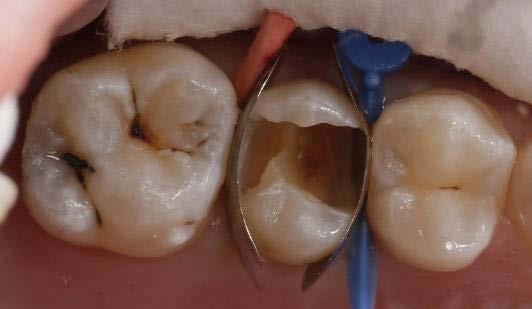

Exploración Intraoral

Presenta un estado oral deficitario. Parcialmente edéntula, con colapso de mordida, migración dental patológica, restauraciones de resina antiguas fisuradas y filtradas, transparencia y exposición de cámara pulpar secundaria a desgastes con pérdida de estructura e integridad de tejido dental importante (Figuras 1 a 4). Portadora a tiempo parcial de prótesis removibles desadaptadas de más de 10 años de antigüedad, refiriendo incapacidad de adaptación a este tipo de prótesis.